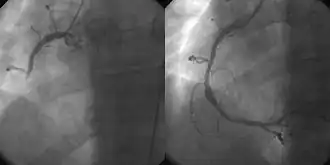

Ангиография правой коронарной артерии больного с трансмуральным инфарктом миокарда

• Коронарная ангиография позволяет исследовать сердце после внутривенного введения контрастного вещества на основе йода через катетер, предварительно обследовав пациента на предмет противопоказаний к йоду. Ангиография может быть назначена после получения аномальных результатов ЭКГ и стресс-тестов, вместе с жалобами на боль и другими характерными симптомами[27][28].